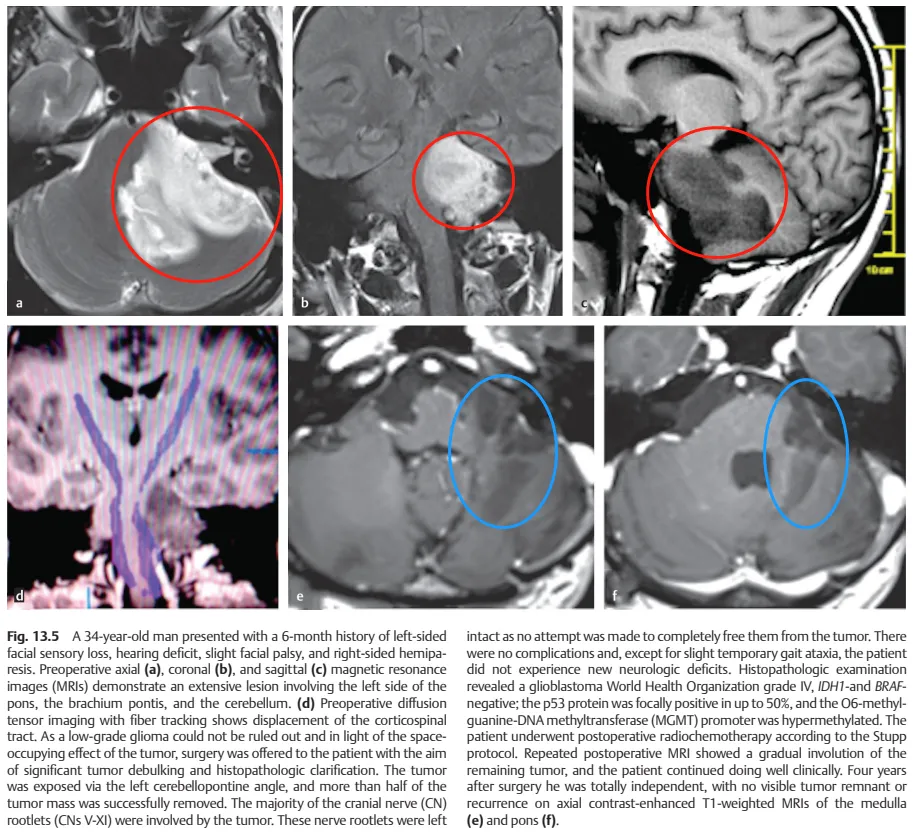

本文分享一例脑干胶质母细胞瘤手术切除后配合辅助放疗4年未复发的案例,出自INC巴教授发表于2020年《Surgery of the Brainstem》的中第13章Adult Brainstem Gliomas(成人脑干胶质瘤)。《Surgery of the Brainstem》该专着则系统详细的介绍了脑干的解剖特点、不同脑干肿瘤手术入路选择及手术案例展示。

INC巴教授文章中的该案例截图